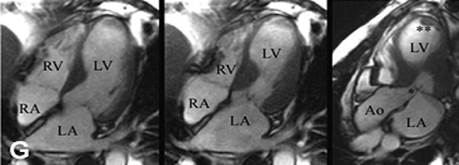

Hình ảnh MRI bệnh Takotsubo 1. Dịch tễ Bệnh Takotsubo chiếm tỉ lệ khoảng 1% - 2% những bệnh nhân được chẩn đoán hội chứng vành cấp, thường xuất hiện ở phụ nữ sau mạn kinh, tỉ lệ nam giới gặp rất ít (< 10%). Ví dụ, trong nghiên cứu lớn đầu tiên tại Nhật Bản trên 88 bệnh nhân: độ tuổi trung bình 67 ± 13 năm, gồm có 76 nữ và 12 nam [11]. Abhishek Deshmukh nghiên cứu tỉ lệ lưu hành bệnh Takotsubo dựa trên dữ liệu bệnh nhân điều trị nội trú toàn quốc tại Mỹ năm 2008. Trong 33.506.402 bệnh nhân nhập viện điều trị có 6837 bệnh nhân được chẩn đoán Takotsubo (0,02%). Tỉ lệ bệnh nhân chủ yếu là nữ (odds ratio là 8.8), trong đó số bệnh nhân nữ > 55 tuổi cao gấp 4,8 lần so với nhóm < 55 tuổi. Các yếu tố có liên quan đến bệnh gồm: hút thuốc, lạm dụng rượu, trạng thái lo âu và tăng lipid máu [2].